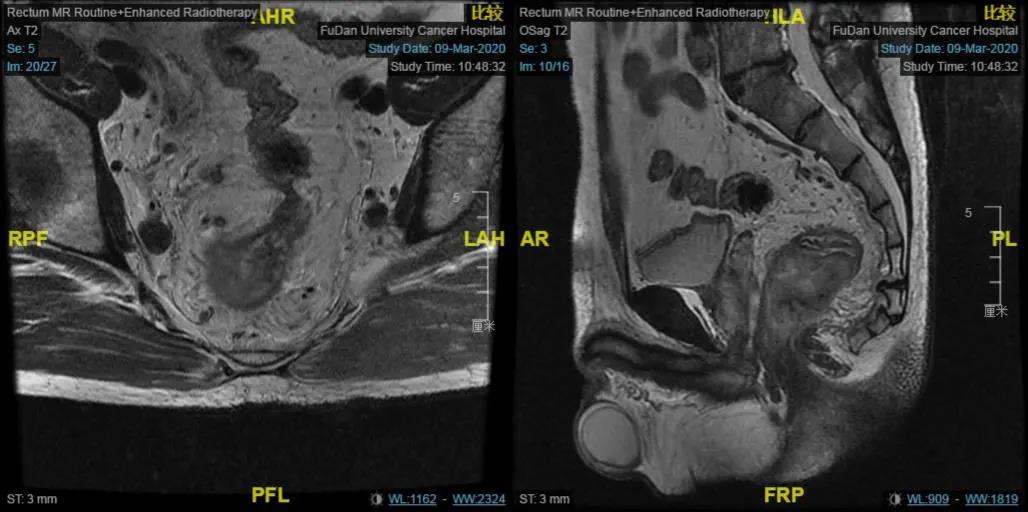

假如你是一名肛肠外科医生,现在有这样一个病例摆在你面前:患者为40岁男性,初诊为肿瘤下缘距离肛门仅有3.5cm的极低位直肠癌,有强烈的保肛和生存意愿。但局部病期较...